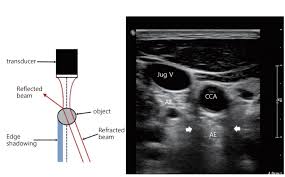

경동맥 초음파 검사란, 초음파 장비를 사용하여 목 부위의 경동맥 상태를 실시간으로 검사하는 방법입니다. 이 검사는 주로 경동맥의 혈류 속도, 혈관의 두께, 그리고 플라크의 존재 여부를 평가하여, 경동맥 초음파 검사로 알 수 있는 병을 진단합니다. 검사 과정은 매우 간단하며, 환자는 편안한 자세로 누운 상태에서 초음파 탐촉자를 목 부위에 대고 진행됩니다. 일반적으로 검사 시간은 10~15분 정도 소요되며, 검사 후 당일에 결과를 확인할 수 있어 빠른 조치가 가능합니다.

경동맥 협착은 경동맥의 내강이 50% 이상 좁아지는 것을 의미하며, 이로 인해 혈류 속도가 급격히 증가하게 됩니다. 경동맥 초음파 검사를 통해 이러한 협착을 발견할 수 있으며, 70% 이상의 협착이 있는 경우 뇌경색 위험이 급증하므로 즉각적인 조치가 필요합니다. 따라서 경동맥 초음파 검사로 알 수 있는 병 중 협착과 폐색을 조기에 발견하는 것은 매우 중요합니다.